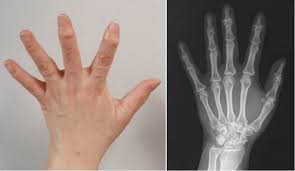

손가락 관절염은 손가락 관절의 연골이 닳아 없어지거나 염증이 생겨 통증과 기능 저하를 일으키는 질환입니다. 이는 주로 노화로 인해 발생하지만, 과도한 사용, 외상, 유전적 요인 등 다양한 원인에 의해 발생할 수 있습니다.

- 골관절염: 연골이 닳아 없어지면서 뼈가 직접 마찰을 일으켜 통증과 경직을 유발합니다.

- 류마티스 관절염: 면역 체계가 자신의 관절을 공격하여 염증을 일으키는 자가면역 질환입니다.

손가락 관절 주변이 붓고 뜨거워질 수 있습니다. 이는 염증으로 인한 반응으로, 손가락을 움직일 때 더 심해질 수 있습니다. 부종이 지속되면 관절이 변형될 위험이 있습니다.

X선, MRI, 초음파 등 다양한 영상 검사를 통해 손가락 관절의 상태를 정확히 파악할 수 있습니다. 이러한 검사는 연골의 손상 정도와 염증의 위치를 확인하는 데 유용합니다.